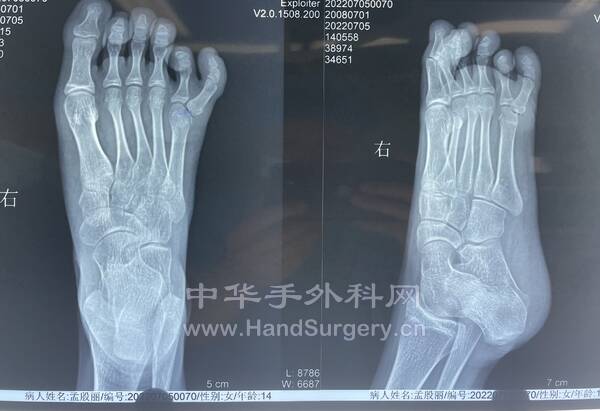

患者女性,14岁,先天双足多趾畸形。